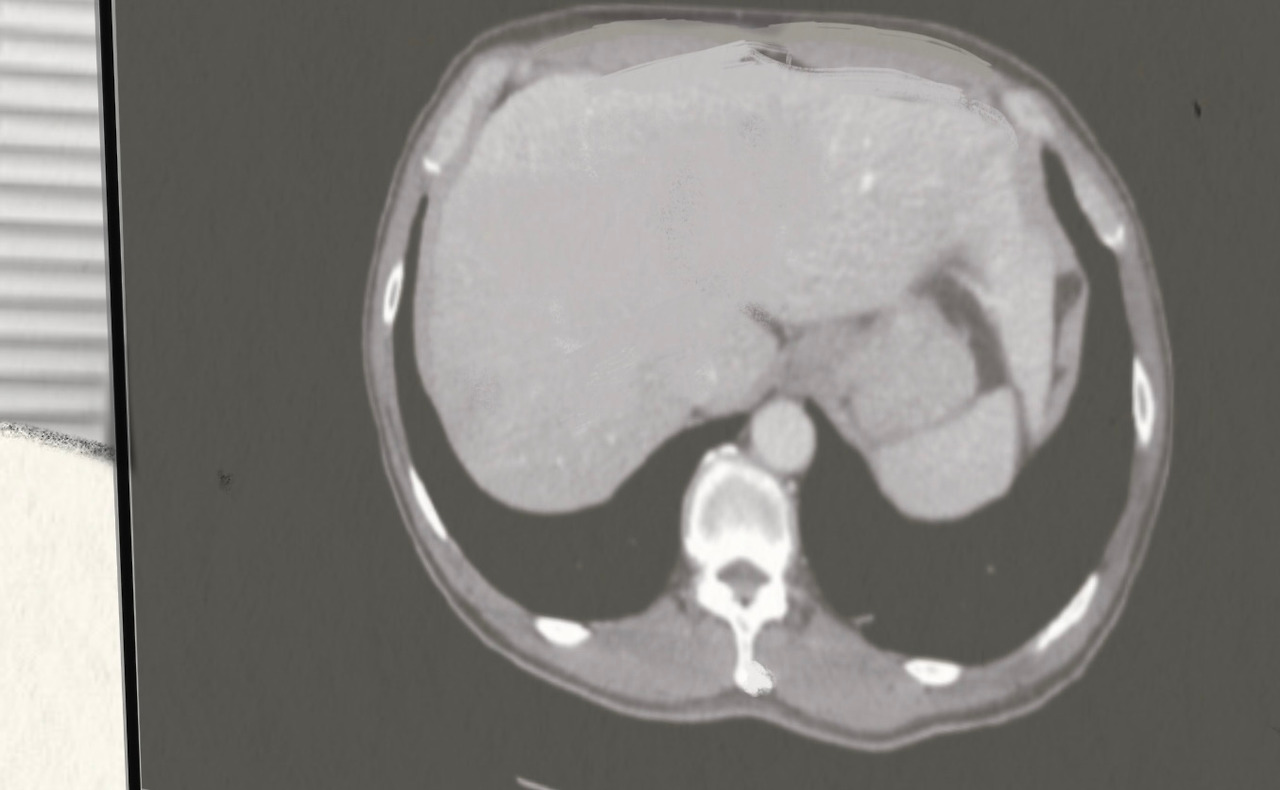

암 덩어리가 있는 부위를 수백 장 CT촬영한다.

그 사진들을 가지고 담당 의사 선생님들이 모여서 분석한다.

33일간 방사선을 암 덩어리가 있는 부위에 최대한 정확하게 쏜다.